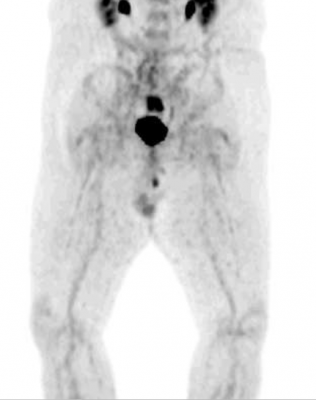

November 15, 2013 — For patients who fail to respond to current first-line and second-line treatments for colorectal cancer liver metastases (also known as salvage patients), radioembolization with Y-90 microspheres could extend survival according to new research published in the November issue of The Journal of Nuclear Medicine. A systematic review conducted by researchers showed that approximately 50 percent of salvage patients have an overall survival of more than 12 months after this nuclear medicine therapy.

Researchers reviewed a total of 13 articles on Y-90 radioembolization as a monotherapy and 13 articles on Y-90 radioembolization as a combined with chemotherapy. Among the studies, disease control rates ranged from 29-90 percent in the monotherapy studies, which involved 901 patients. In the studies in which Y-90 radioembolization was combined with chemotherapy, involving 472 patients, disease control rates ranged from 59-100 percent.

“From the studies included in this systematic review, survival proportions of approximately 50 percent were found,” said Rosenbaum. “Therefore, in this group of salvage colorectal cancer liver metastases patients who otherwise have no regular treatment options and a life expectancy of less than six months, Y-90 radioembolization seems to be a hopeful treatment option.”